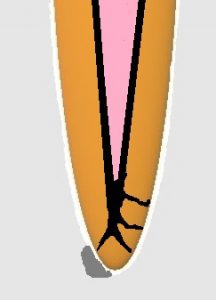

おわかりいただけるだろうか?根尖が3股に分かれている上に、側枝あり。

リーマー・ファイルでは3根管を洗浄できない。

そこで、バイブリンジ、エンドアクチベーターが役立ちます。